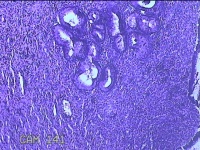

宫颈赘生物

性别

女

年龄

49岁

临床诊断

人乳头瘤病毒感染

一般病史

宫颈HPV阳性TCTLSLL

标本名称

大体所见

灰白粉红色肿物1.2x0.8x0.2cm两个,表面光滑。